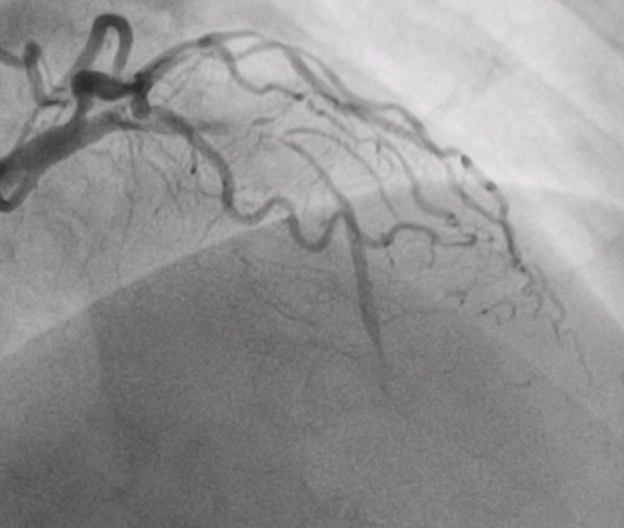

术前患者冠脉造影

安徽人陈先生远在新疆工作,因快走后出现胸闷症状且越来越严重于当地医院就诊,冠脉造影显示冠状动脉多支多处严重弥漫性狭窄,病情十分凶险,医生建议他立即开胸做搭桥手术,但是由于血管病变太严重,手术风险极高,很有可能下不来手术台。陈先生和家人一筹莫展之际,有人向他们推荐了捷克论坛 心血管内科三病区潘宏伟主任团队,了解到潘宏伟主任团队擅长冠脉介入诊疗,尤其是在疑难复杂的病变方面,临床经验非常丰富,于是陈先生与家人决定连夜打“飞的”往湖南求诊。

陈先生入院后,潘宏伟主任团队对其病情进行了全面评估,制定了详细周密的诊疗计划,于1月27日行介入支架治疗开通了几乎完全闭塞的前降支血管,术后效果“立竿见影”,陈先生的胸闷症状立马消失了。由于陈先生冠脉多支多处弥漫性狭窄严重,要想修复所有的血管还需要在多处植入药物球囊,手术难度较大,加上年后就可以享用集采的价格,于是建议他调理两月再来。近日,陈先生从遥远的新疆再次打“飞的”来长沙行第二次手术,4月12日潘宏伟主任团队采用了支架+药物球囊的组合方式,完美的修复了非常复杂的冠状动脉,术后经过精心护理,陈先生于4月15日康复出院。